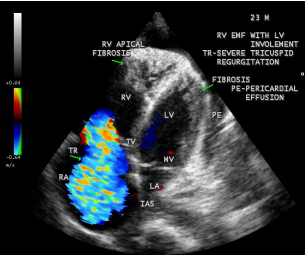

Case 2 (Right ventricular endomyocardial fibrosis in Tuberculosis) A 23-year old male was admitted with sudden onset of ascites for one-month duration. He was treated for pulmonary tuberculosis 3 years back with a positive sputum AFB (acid fast bacilli). Blood chemistry revealed as ( Total count-7400 cells/cu.mm of blood ( normal-4000 to 11000 cells/cu.mm of blood), polymorphs -70% (normal- 40 to 75 %), lymphocytes-22%(normal-20 to 40%), eosinophils-8% (normal- 1 to 4%), ESR (erythrocyte sedimentation rate)-10 to 22 mm/hour ( normal- 0 to 15mm/hour), platelets-2.5 lakhs/cu.mm of blood and a mild elevation of serum bilirubin-total-2mg/dl(normal---up to 1.2 mg/dl) direct-1.2mg%(normal—upto—0.3 mg/dl), indirect-0.8mg%(normal – upto 0.9 mg/dl). Total serum proteins 5.2gm% (normal -6.6 to 8.3 gm/dl), albumin-3.2gm% (normal- 3.5 to 5.0 gm/dl), globulin -2.0gm%(normal 2.5 to 3.5 gm/dl ), urea-39 mg%(normal 15-50 mg/dl), creatinine-0.1mg%(normal- 0.7 to 1.4mg/dl), sugar-112 mg/dl random (normal – 80 to120 mg/dl- random sample). Ascites fluid tapping revealed an exudate (protein-3 gm%) and cytology revealed no malignant cells. Ascites fluid adenosine deaminase (ADA)activity revealed 10.4 U/L (normal < 40>Figure 8. His pulse rate was 108 bpm and blood pressure 100/70 mmHg. Auscultation revealed clear lung fields and no cardiac abnormalities. ECG revealed no arrhythmias and X-ray chest showed right- sided pleural effusion and extensive calcification over the cardiac shadow as shown in Figure 9. Transthoracic echocardiography revealed apical fibrosis of right ventricle, moderate pericardial effusion, right atrial dilatation as shown in Figures 10 and 11, suggesting right ventricular endomyocardial fibrosis and severe tricuspid regurgitation as in Figure 12 indicates coexisting pulmonary hypertension due to pulmonary damage caused by tuberculosis as shown in Figure 13 and free RV outflow tract as in Figure 15. Patient was treated with antituberculous drugs, antifailure measures such as digoxin and diuretics, ascites fluid tapping and antibiotics. He showed mild improvement in his symptoms.

Figure 11: Apical four chamber view suggesting RV (right ventricular) apical fibrosis, RA dilatation and severe tricuspid regurgitation suggesting right ventricular endomyocardial fibrosis with an extension of fibrosis in the LV apex

Figure 12: Apical four chamber view showing the RV apical fibrosis with mild pericardial effusion in a 23-year old male with tuberculosis.